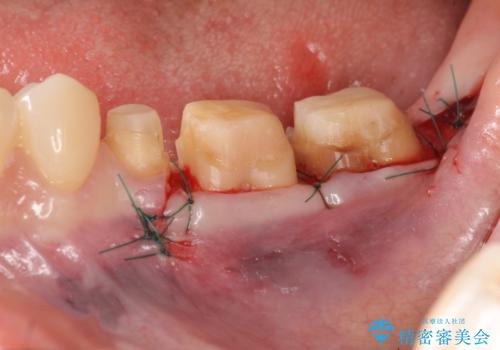

- 左下の歯が虫歯により崩壊し、歯ぐきからの出血も毎回歯ブラシを行う際に出ることから治療を求めて来院されました。

現在装着されているクラウンを除去したところ、クラウンマージンが歯肉縁下となり歯ぐきの炎症が認められたため再度オールセラミッククラウンを製作する前に歯周外科手術を行い歯ぐきの状態を改善しました。